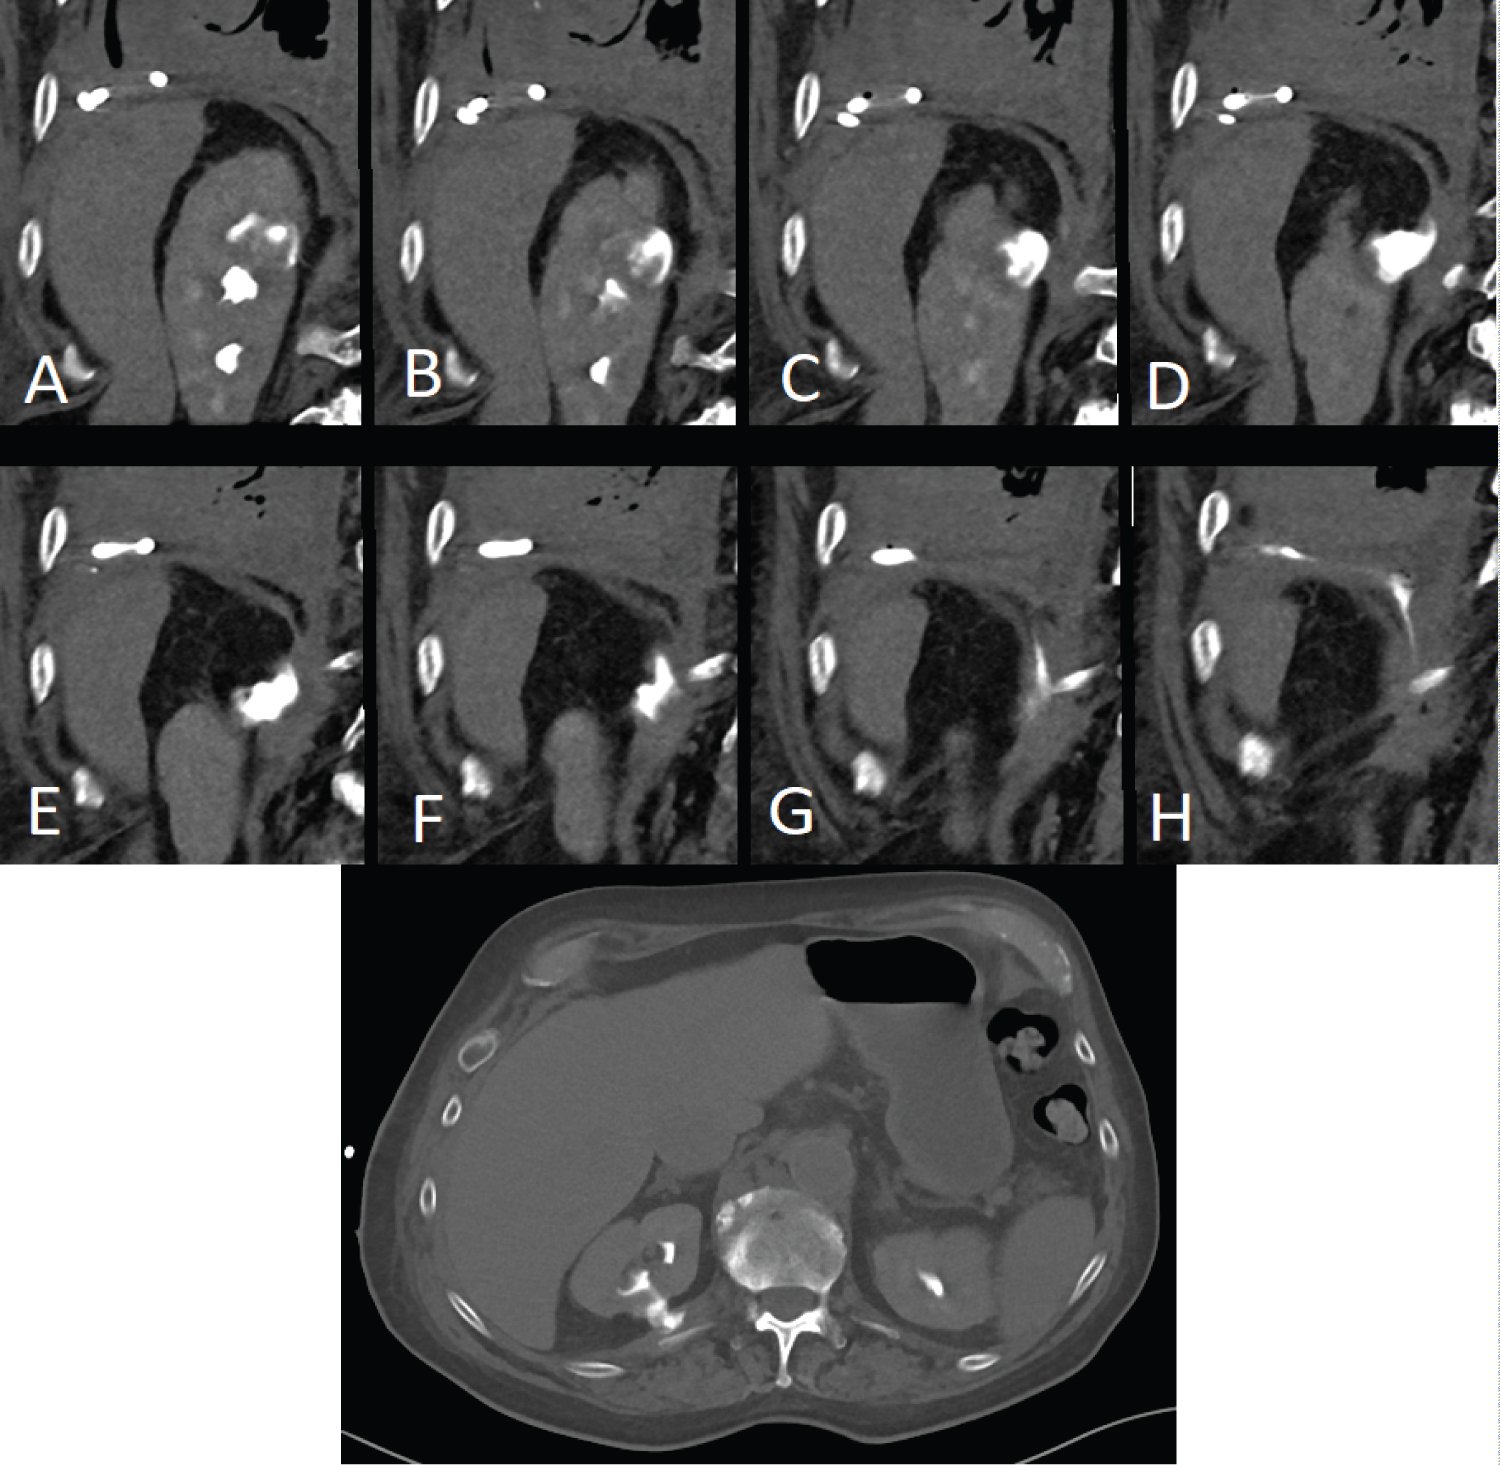

An 83-year-old male who presented with a growing right-sided mass, previously biopsied and shown to be an oncocytoma (Figure 1). Given the growth from 2.8 cm to 3.6 cm over 8 months, there was concern for sampling error and after multidisciplinary discussion percutaneous ablation was pursued. The patient underwent MWA of the 2.9 × 3.6 cm utilizing 3 probes at 90W for 10 minutes (Long Perseon Microthermx®) with an expected ablation zone of 4 × 5.3 cm (Figure 2). Three months after the ablation, the patient developed shortness of breath secondary to a pleural effusion and presented to OSH where he underwent multiple thoracenteses. Given the refractory nature of his effusions, he underwent placement of a tunneled pleural catheter for management of this high volume, refractory effusion. At the time of placement of this tube, urinothorax was considered as an etiology of this effusion and a sample was sent for fluid creatinine, which was 52 mg/dl (concurrent serum creatinine was 0.8 mg/dl). An excretory phase CT demonstrated accumulation of contrast in the chest, confirming the diagnosis of with urinothorax (Figure 3). A percutaneous nephroureteral (PCNU) tube was then placed for urinary diversion and output from the chest tube abated. One month later, the PCNU was removed at outside hospital with subsequent recurrence of the urinothorax. Owing to significant morbidity and frustration the patient opted to undergo right nephrectomy rather than additional stenting.

Figure 3: Serial coronal images (A-H) and axial CT (I) from a CT in excretory phase shows accumulation of contrast in the pleural space. View Figure 3